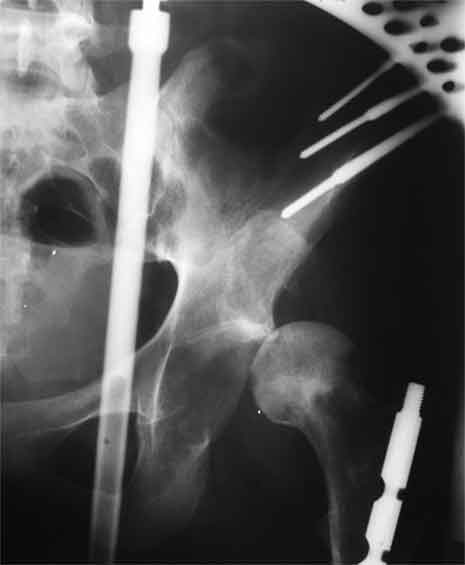

Насчет 8 см согласен с А.Н. Челноковым, это наверное ортопедическое за счет приводящей, сгибательной контрактуры и, возможно, колена. на ликвидацию укорочения у нас обычно уходит около 2-х нед. снимки в приложении, возможно не очень показательные, но других с ходу не нашел, завтра еще поищу.